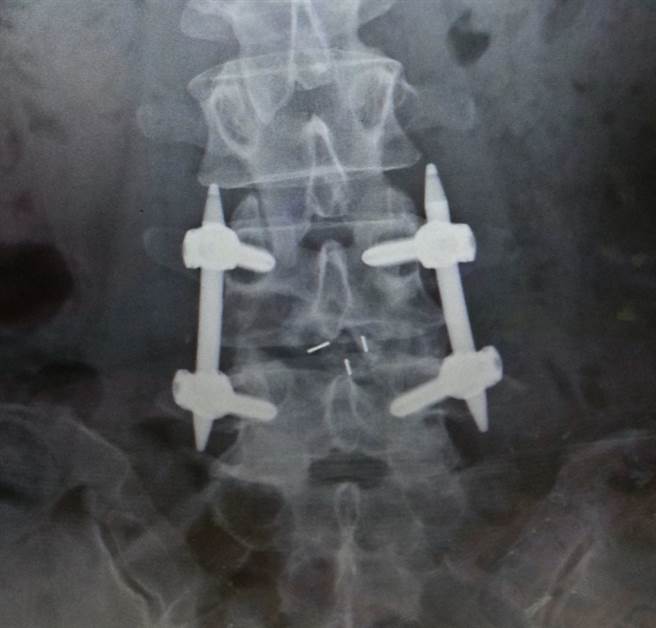

大部分的椎间盘退化或骨刺皆可用微创手术治疗。现今的脊椎微创手术,可适用于椎间盘退化突出合併的神经压迫,脊椎狭窄造成的神经性跛行,或是脊椎滑脱与脊柱结构不稳定所产生的症状。

张先生经过微创手术处理后,术后立即感觉到腰部的酸痛感明显改善,而且脚踝活动自如,原本无力的双脚也日益改善,行走能力逐渐增强,预计数月后可完全恢復正常,重新回到工地工作。